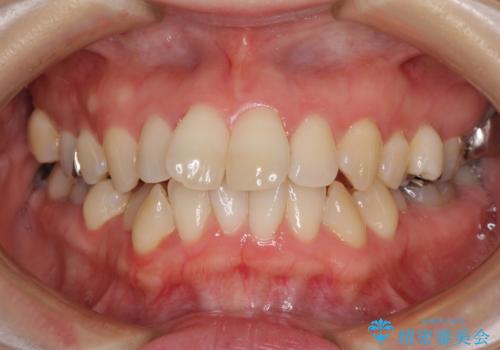

- 奥歯のむし歯を気にして来院された患者様です。

当初は右下の虫歯治療のみを希望されていましたが、虫歯治療に際して部分矯正が必要であったため、治療方法について説明をすると、全体的に歯列不正が気になっているとのことで、全顎矯正を検討することとなりました。

口元の突出感とデコボコがあり、上下左右の小臼歯4本を抜歯して矯正治療を行う方針としました。(右上は欠損のため計3本抜歯)